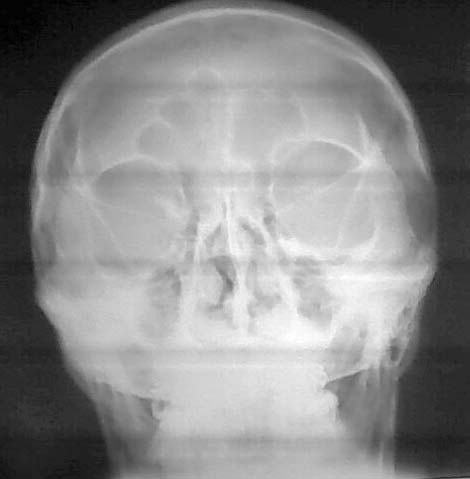

标题: X6548:头颅外伤

额顶部外伤3小时,请问箭头所指正常吗